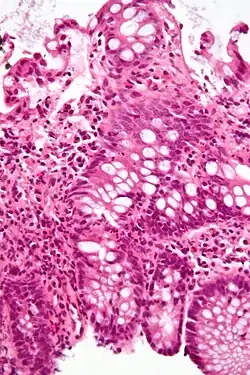

Na medicina, doença inflamatória intestinal (DII) é um grupo de condições inflamatórias do cólon e intestino delgado. Os principais tipos de DII são doença de Crohn e colite ulcerativa.[1][2][3]

O diagnóstico se dá geralmente através de colonoscopia com biópsia das lesões patológicas.